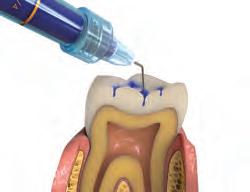

FOR VITAL PULPOTOMY IN PRIMARY TEETHEXPANDED APPLICATION

1. Control bleeding. Use Dento-Infusor tip with ViscoStat or Astringedent™ hemostatics.1 Use sterile water for this procedure.

3. Apply a thin layer of Ultra-Blend™ plus liner.

4. Apply Ultra-Etch™ phosphoric acid or Peak™ SE Primer.

5. Apply Peak™ Universal Bond bonding agent.

6. Use your preferred restorative material for definitive restoration. PROTECTION

1. Fei AL, Udin RD, Johnson R. A clinical study of ferric sulfate as a pulpotomy agent in primary teeth. Pediatr Dent. 1991;13(6):327-32.